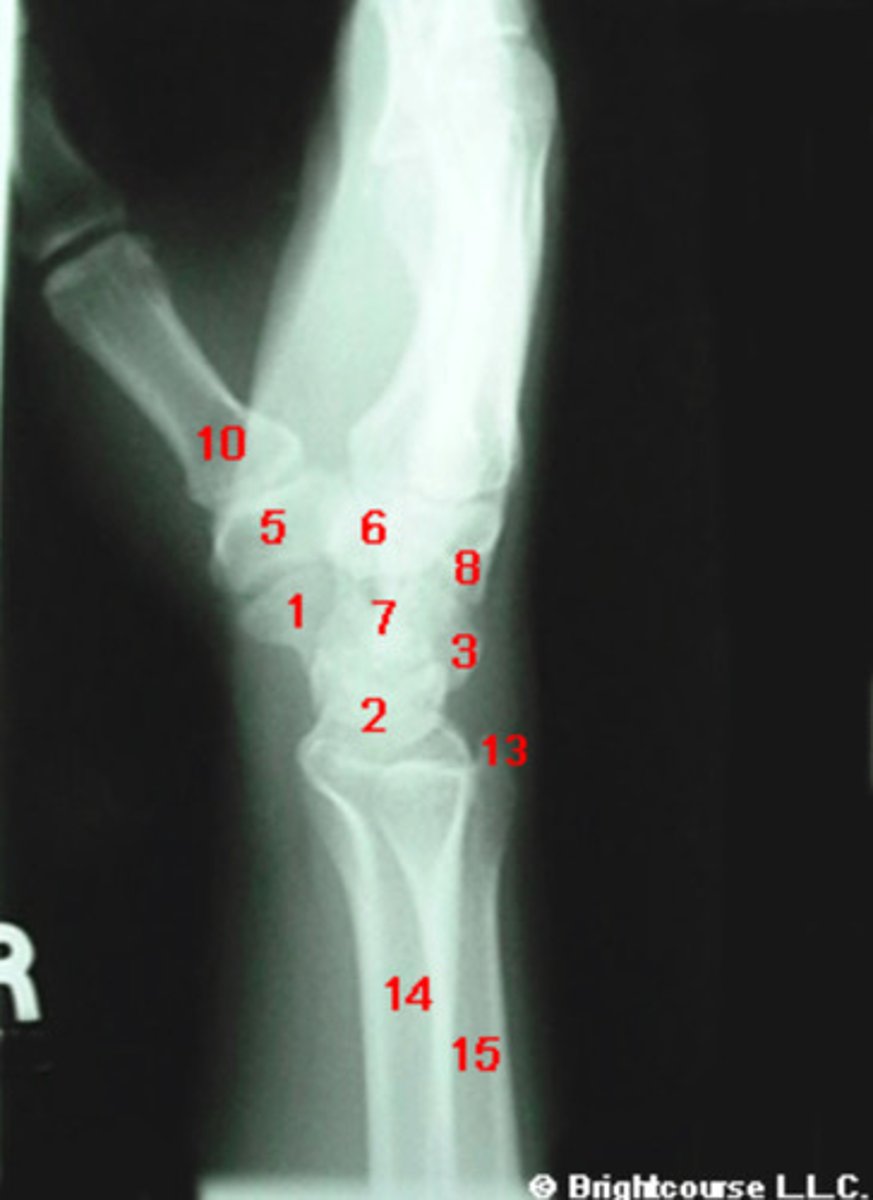

What structure is indicated by number 7?

What structure is indicated by number 1?

What structure is indicated by number 2?

What structure is indicated by number 3?

What structure is indicated by number 4?

What structure is indicated by number 5?

What structure is indicated by number 6?

What structure is indicated by number 8?

What structure is indicated by number 13?

What structure is indicated by number 12?

What structure is indicated by number 10?